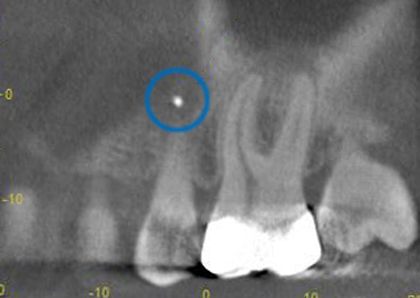

Vor der Zahnwurzel des kleine Backenzahnes hat sich ein "Fremdkörper" versteckt, der auf dem konventionellen Röntgenbild nicht sichtbar ist.

Durch die räumliche Verschiebung im 3D-Röntgen-Bild können wir diesen Fremdkörper identifizieren und Sorge tragen, dass dieser entfernt werden kann.